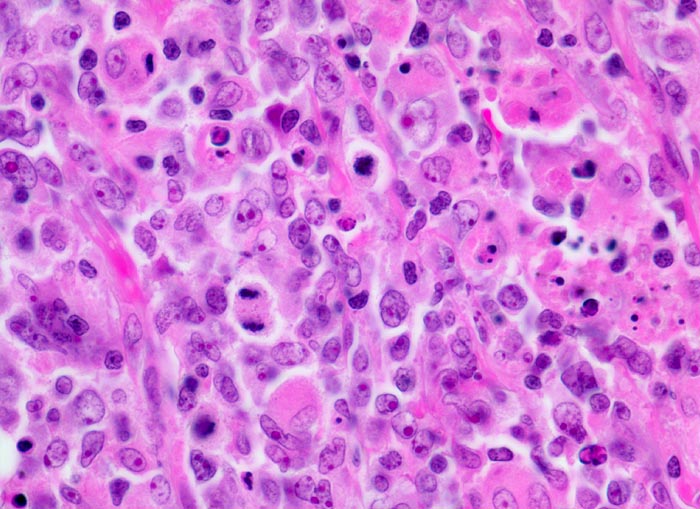

Diffuses grosszelliges B-Zell Lymphom

Mittelgrosse stark polymorphe Tumorzellen mit unregelmässig geformten, teils lobulierten oder eingekerbten Kernen. Oft sind mehrere randständige Nukleolen erkennbar (Zentroblastische Variante). Schmaler Zytoplasmasaum. Zahlreiche Histiozyten mit reichlich eosinophilem Zytoplasma und ovalen Kernen ohne Atypien. Mehrere Mitosen und Apoptosen als Ausdruck der raschen Zellproliferation.

Magenlymphom mit Befall abdominaler Lymphknoten.

630